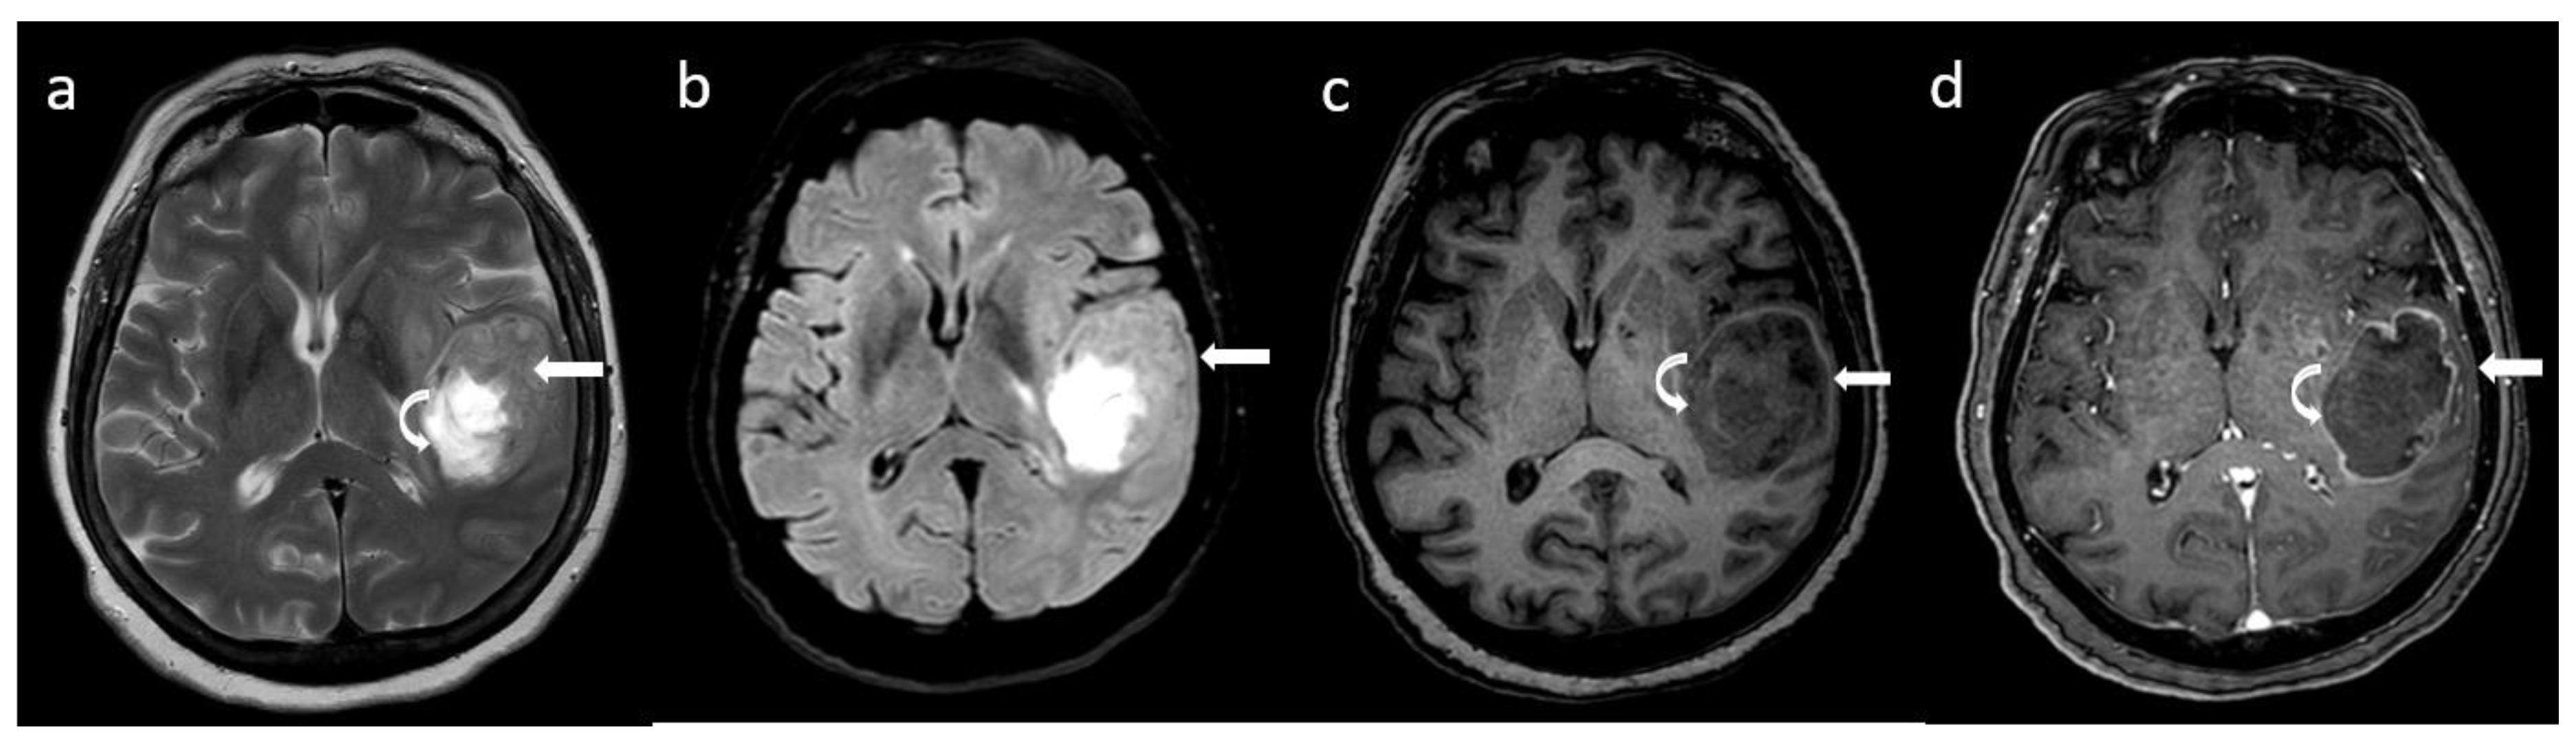

- Broen, M.P.G.; Smits, M.; Wijnenga, M.M.J.; Dubbink, H.J.; Anten, M.H.M.E.; Schijns, O.E.M.G.; Beckervordersandforth, J.; Postma, A.A.; van den Bent, M.J. The T2-FLAIR mismatch sign as an imaging marker for non-enhancing IDH-mutant, 1p/19q-intact lower-grade glioma: A validation study. Neuro-Oncology 2018, 20, 1393–1399. [Google Scholar] [CrossRef] [PubMed]

- Patel, S.H.; Poisson, L.M.; Brat, D.J.; Zhou, Y.; Cooper, L.; Snuderl, M.; Thomas, C.; Franceschi, A.M.; Griffith, B.; Flanders, A.E.; et al. T2-FLAIR Mismatch, an Imaging Biomarker for IDH and 1p/19q Status in Lower-grade Gliomas: A TCGA/TCIA Project. Clin. Cancer Res. 2017, 23, 6078–6085. [Google Scholar] [CrossRef]